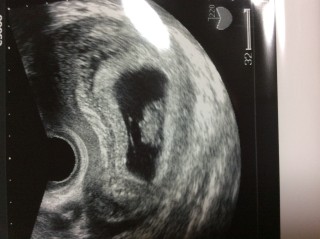

7週に心拍確認して一週間後のものです!まだ、不安で胸がキュンキュンする中、初めて腹部エコーしました。元気でいてくれてよかったー。手足があるようですが私には判断つきません‥‥。つわりはまだ大したことないです。

7週→CRL=9.5、8週→CRL=15